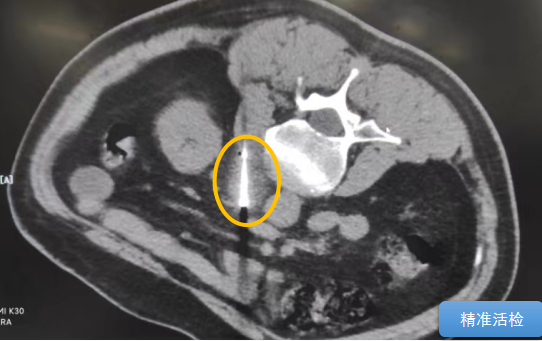

術中陳寶瑩主任、李鐵柱教授、兀云飛醫生、魏東紅技師、汝平護士協調配合,夾縫進針難度雖大,但在CT引導下逐步進針,精準到位,順利活檢取得組織,由于腫瘤較大,為了提高消融效率,平行置入兩根冷凍消融針,同時啟動冷凍消融,術中清晰觀察到冰球完全覆蓋病變,患者沒有任何不舒服,治療中還可以和醫生聊天。

術后病理結果顯示為印戒細胞癌。冷凍消融1個月后,復查增強CT顯示病變無任何強化,達到了完全消融的目的。